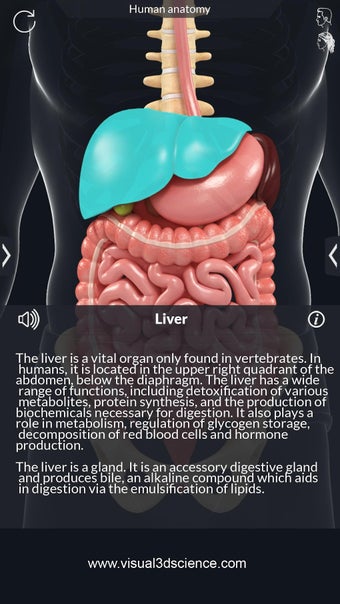

De camera kan worden verplaatst om een ander beeld van elk deel te krijgen.

Je kunt alle informatie over de organen krijgen, inclusief hun locatie, hun functie en hoe ze eruitzien.